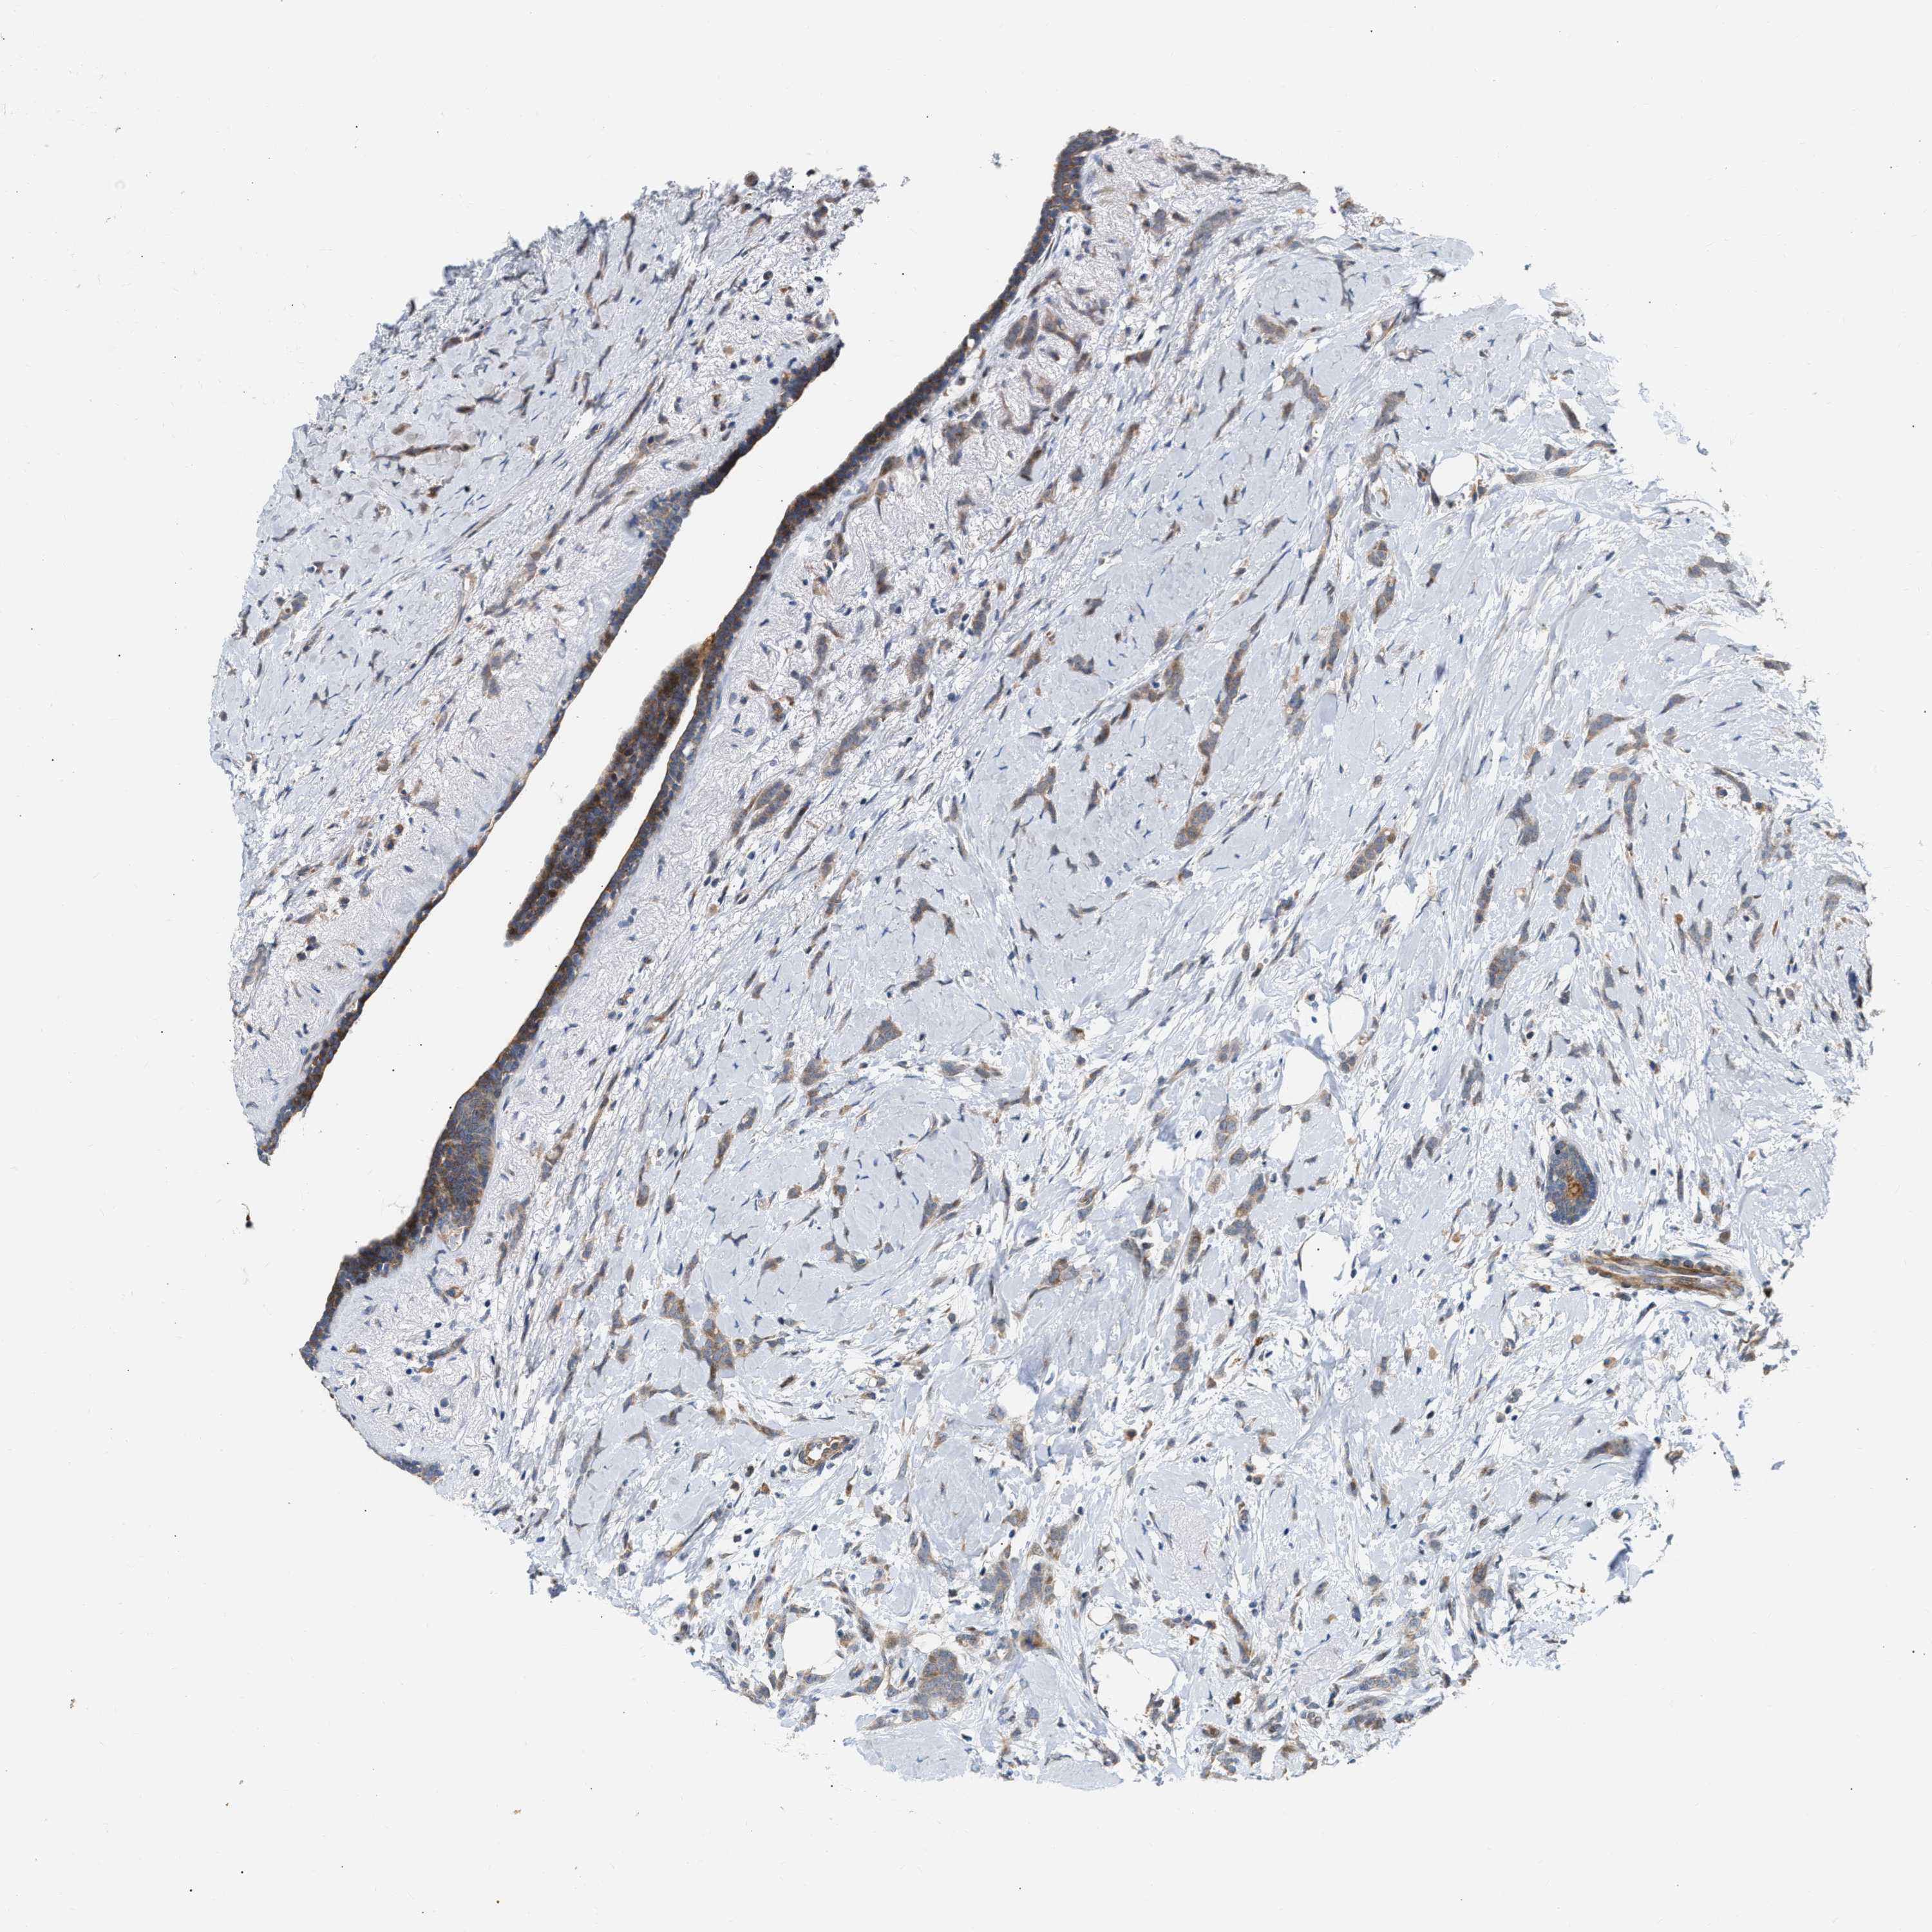

CANCER BREAST CANCER Show tissue menu

BRCA TCGA BRCA VALIDATION PROTEIN EXPRESSION